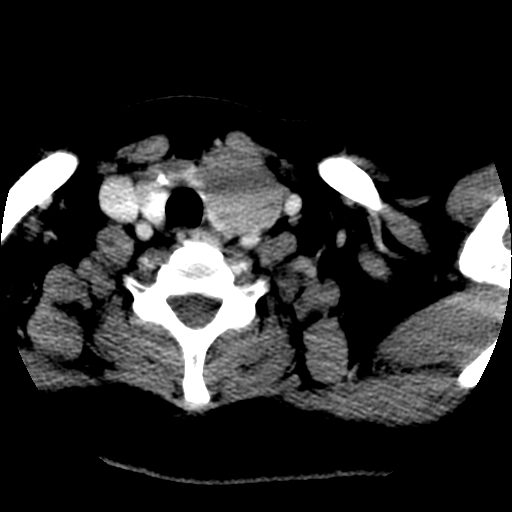

左右叶都有,峡部也受累,有钙化,考虑结甲可能性大。

考虑右叶结节性甲状腺肿,伴左叶钙化。主要(1)密度均匀,边境清。(2)病灶与血管界限清。

边界清,无明显强化,考虑考虑甲状腺腺瘤